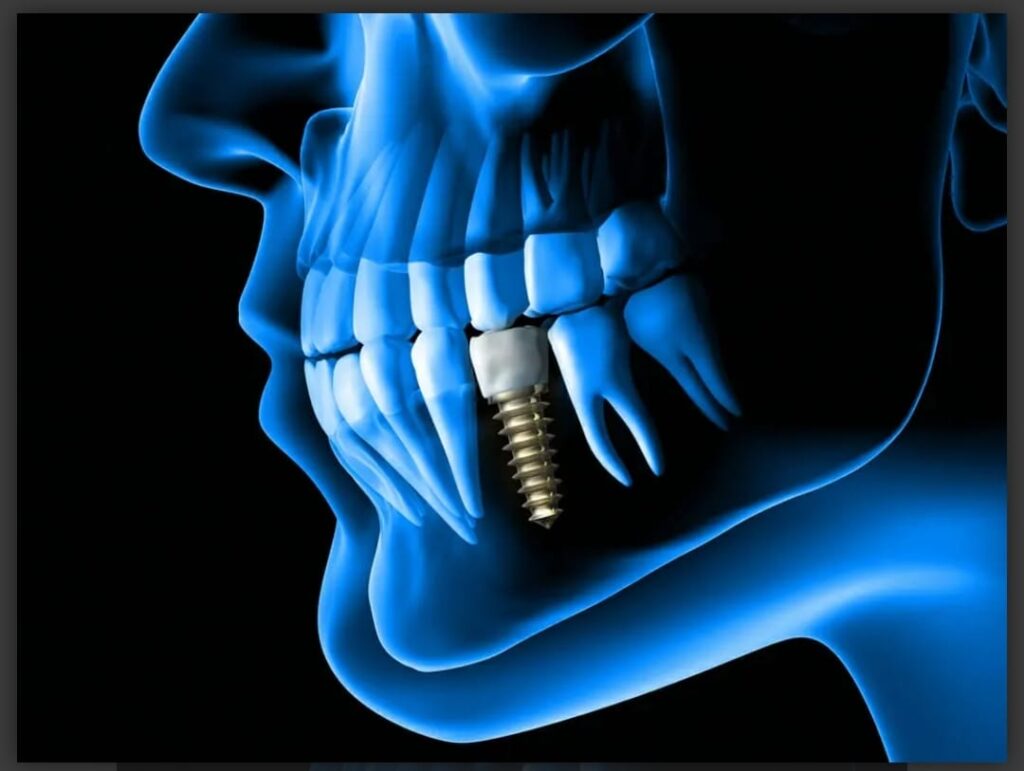

Dental Implants

Dental implants are a long-term solution to tooth loss, providing a natural-looking smile and restoring proper mouth function. Our expert team ensures precise placement and comfortable recovery.